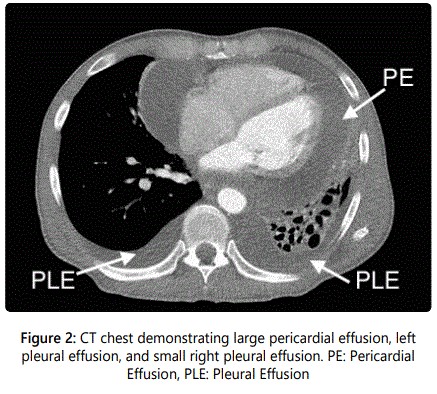

A 54-year-old gentleman with recently diagnosed Stage IIIB squamous cell carcinoma of the lung with metastases to the lymph nodes had a transthoracic echocardiograph (TTE) performed for evaluation of progressive dyspnea on exertion. A large pericardial effusion causing tamponade physiology was noted on TTE and the Computerized Tomography (CT) image of the thorax (Figures 1 and 2). Following a pericardi ocentesis, a repeat TTE was performed which showed the presence of a left atrial mass (Figure 3). The mass was initially reported as a 1.3x0.5 cm pedunculated mobile left atrial mass arising from the left atrial appendage prolapsing in the mitral orifice in diastole before further assessment with a transesophageal echocardiogram (TEE) was performed. The TEE demonstrateddirect invasion of the mass from the left upper pulmonary vein into the left atrial appendage with minimal residual flow of that pulmonary vein and complete opacification of the left atrial appendage as well as invasion of the superior vena cava (Figure 4). The mobile mass in the left atrium was a strand of tumor that extended from the edge of the left atrial appendage (Figures 5 and 6).